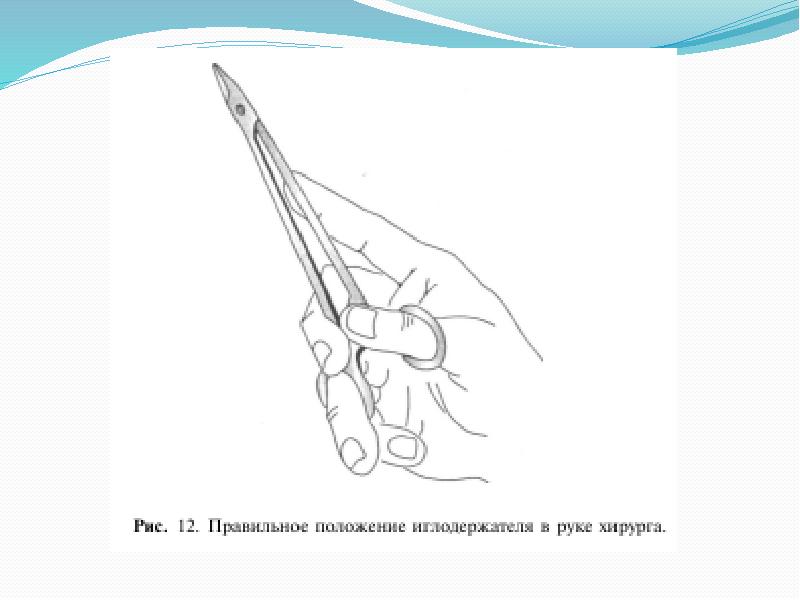

- 9. Правильное положение стандартного иглодержателя в руке хирурга должно быть следующим: